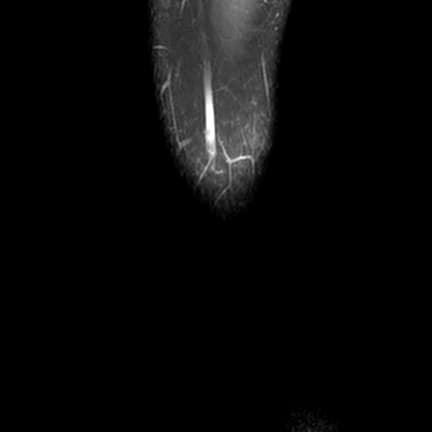

Coronal PD fat sat

MRI•Coronal PD fat sat•1 / 16

Ca bệnhXé dạng xô hình thùng ở sụn chêm bên

Xé dạng xô hình thùng ở sụn chêm bên

- Xé dạng xô hình thùng ở sụn chêm bên với sự di lệch của mảnh sụn chêm về phía trong vào khe gian lồi cầu (bucket handle tear of the lateral meniscus with the displacement of the meniscal fragment medially to the intercondylar notch).

Xé dạng xô hình thùng là một dạng rách bị di lệch từ thân sụn chêm vào khe gian lồi cầu. Thường gặp ở sụn chêm trong, khác với trường hợp này là tổn thương ở sụn chêm bên.

- "Chụp cộng hưởng từ (MRI) cho thấy 'dấu hiệu dây chằng chéo trước kép' hoặc 'dấu hiệu mất hình dạng sụn chêm liên tục' là các dấu hiệu hình ảnh quan trọng để chẩn đoán rách dạng xô hình thùng."

Rách dạng xô hình thùng là một dạng rách dọc dọc theo chiều dọc của sụn chêm, thường xảy ra do chấn thương xoắn ở những người trẻ và hoạt động nhiều. Tổn thương làm tách rời phần trong của sụn chêm, khiến mảnh rách di chuyển vào khe gian lồi cầu, trên cộng hưởng từ (MRI) có thể tạo thành hình ảnh giống như dây chằng chéo trước — được gọi là 'dấu hiệu dây chằng kép'. Trường hợp này liên quan đến sụn chêm bên, ít gặp hơn so với sụn chêm trong, chỉ chiếm khoảng 10–20% các trường hợp rách dạng xô hình thùng. Các phát hiện đi kèm như dịch khớp, rách sụn chêm trong và thay đổi tín hiệu dây chằng chéo trước có thể làm phức tạp thêm lâm sàng. Can thiệp nội soi khớp sớm thường được yêu cầu để phục hồi chức năng đầu gối và ngăn ngừa thoái hóa thêm.